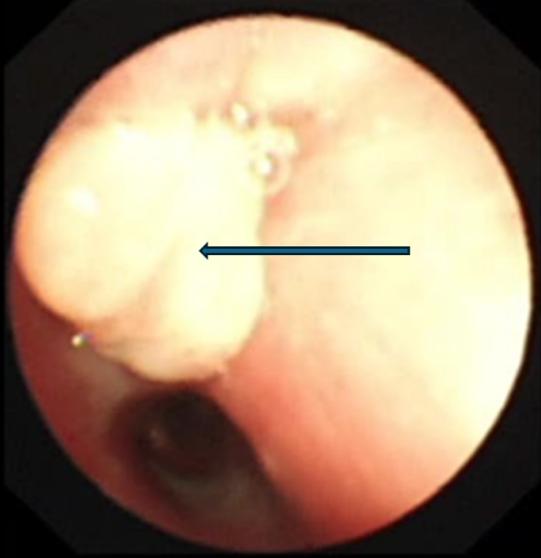

支气管镜下的景象触目惊心:乐乐右主支气管管腔内满是脓性分泌物,且增生的肉芽组织堵塞了右上叶支气管开口。在更深处,一个看似尖锐异物死死堵住了右中间支气管管腔。

支气管镜检查显示右中间段支气管异物堵塞,镜下看似尖锐,表面大量黄绿色分泌物附着

在呼吸科支气管镜室,张东伟主治医师和叶颖龙主管护师紧密配合,小心清理了分泌物,最终用异物钳成功钳取出异物——竟是一颗草莓味糖果的包装纸!展开测量,长度接近3.5厘米。